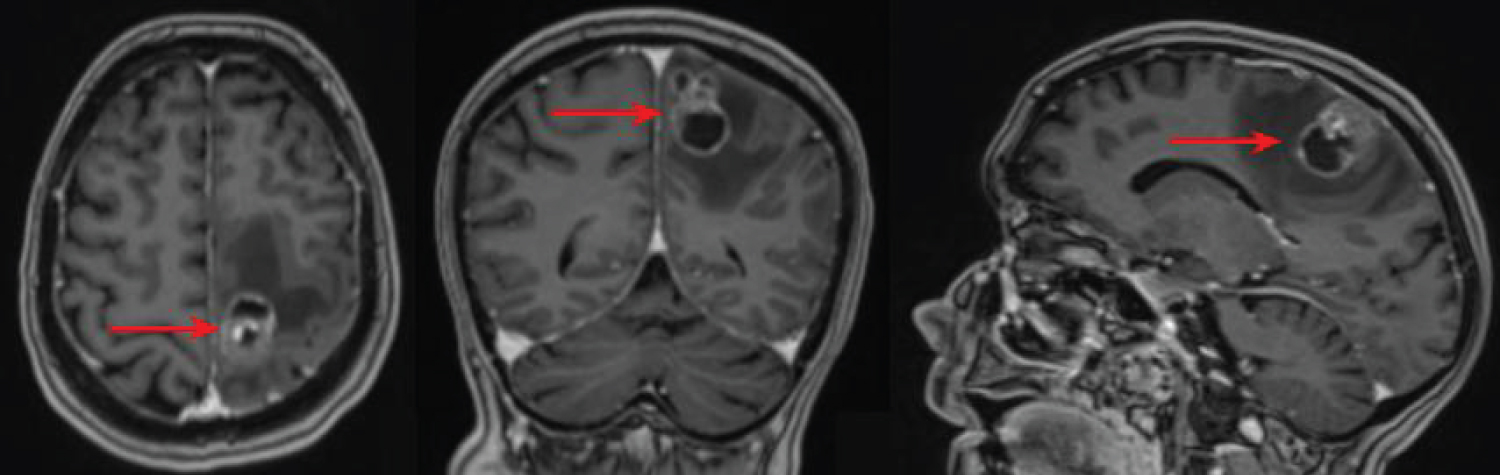

A 60-year-old female presented with a history of endometrial carcinoma and right-sided weakness of the arm and the leg. MRI scan revealed a left parietal lesion that had contrast enhancement and marked edema (Figure 1). The radiological diagnosis was metastasis. Due to the proximity to the motor cortex, an intraoperative imaging method was necessary for preserving motor function.

Figure 1: Preoperative MRI, T1 gadolinium-enhanced sequence. The tumor is marked with the red arrows. View Figure 1